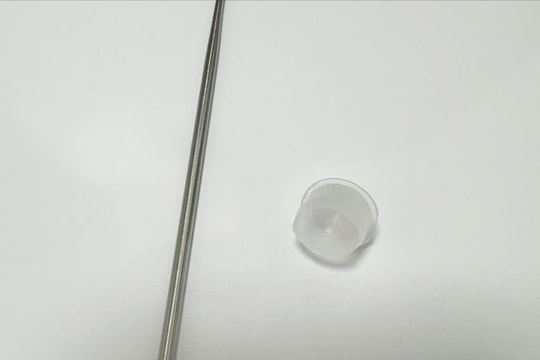

Cứu sống bệnh nhân bị đinh thép xuyên khí quản

08/08/2025 07:49

Mới đây, tại Khoa Cấp cứu - Bệnh viện Trung ương Quân đội 108, tiếp nhận một ca vết thương khí quản xuyên thấu hiếm gặp, tổn thương phức tạp, đe dọa trực tiếp đến tính mạng người bệnh.